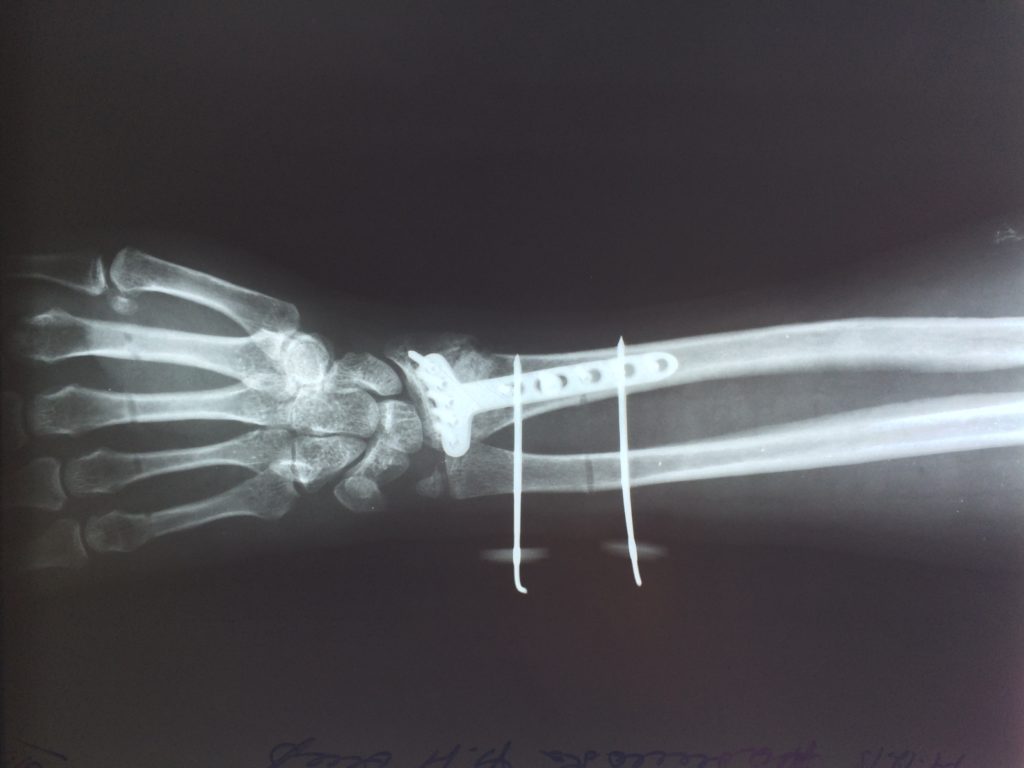

Операция - открытая репозиция, остеосинтез лучевой кости пластиной с костной ксенопластикой материалом "Остеоматрикс". На контрольных снимках в три месяца имеется консолидация перелома, миграции фиксатора нет, имеется остеоинтеграция ксенопластического материала.

Отдаленные результаты через 3 (три) месяца: